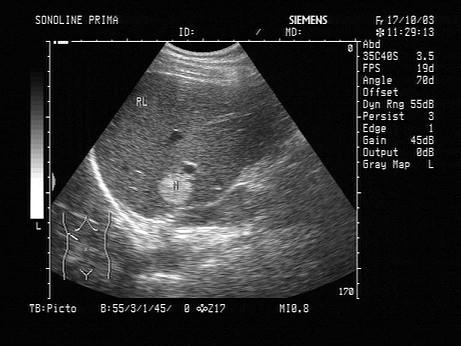

女,38岁。根据超声声像图,可诊断为?(?)A.肝脓肿B.肝血管瘤C.肝癌D.局限性脂肪肝E.肝内钙化灶

问题 女,38岁。根据超声声像图,可诊断为?(?)

选项 A.肝脓肿 B.肝血管瘤 C.肝癌 D.局限性脂肪肝 E.肝内钙化灶

答案 B